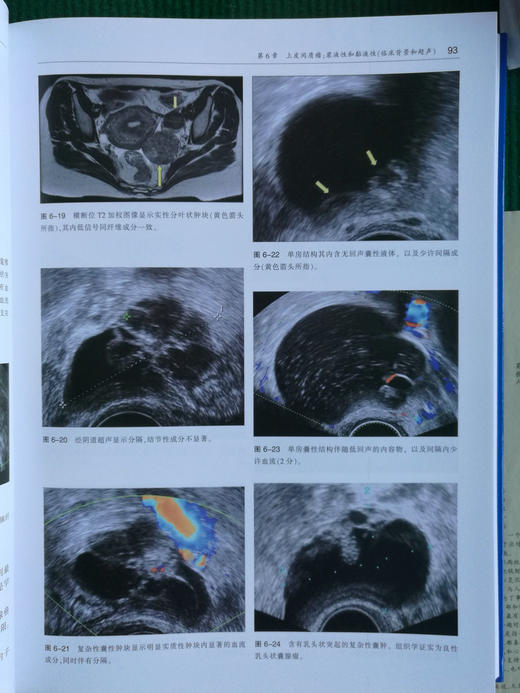

全书分为5大部分,30章,主要内容包括:卵巢肿瘤的流行病学、组织病理;卵巢非肿瘤性病变的临床特征和超声表现,以及CT和MRI诊断;各种良性肿瘤(如上皮间质瘤、卵巢良性上皮间质瘤、卵巢性索间质肿瘤、卵巢畸胎瘤、卵巢良性精原细胞肿瘤等)的临床特征和CT、MRI诊断;交界性和恶性肿瘤的临床特征和诊断方法;以及卵巢肿瘤影像学的未来展望(如附件肿块的三维超声、卵巢肿瘤的三维超声分类、利用公式化量表自动对卵巢肿瘤进行定性和分类等)。